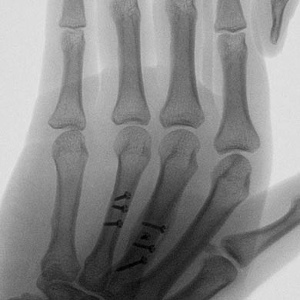

Example X-Ray Images

Repair of Metacarpal Fractures with Screws